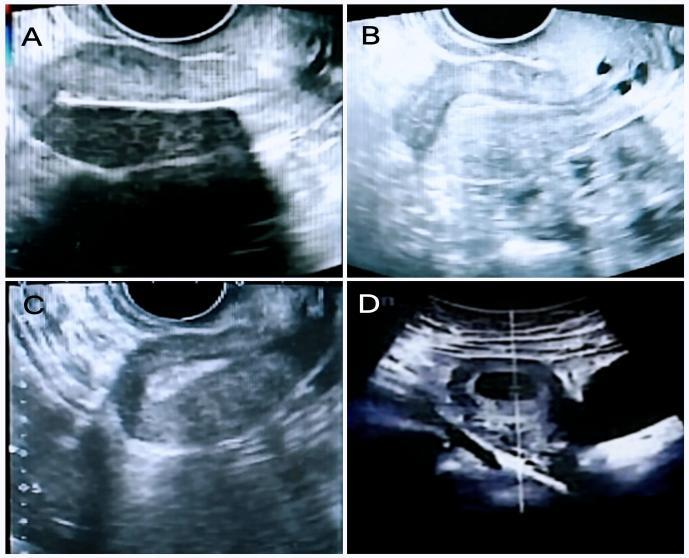

Figure 4.jpegA: 3.7 mm endometrium before PRP intrauterine perfusion; B: 5.9 mm endometrium after the first PRP intrauterine perfusion; C: 8.6 mm endometrium after the second PRP intrauterine perfusion; D: Confirmation of intrauterine pregnancy 4 months after PRP completion.